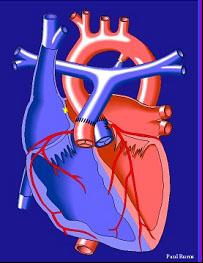

(二)大血管外科治疗:常规开展大血管外科开放性,包括高难度如Bentall+Sun氏;微创经股动脉切开主动脉人工覆膜支架血管腔内成形术,使主动脉夹层(A、B型)的急危重症患者得到有效治疗。

(四)复杂先心病治疗:常规开展各种先天性病外科,并成功开展复杂先心如单心室、心室双出口、大动脉转位及肺动脉闭锁治疗,了一支知识、临床技能强的先心外科队伍。